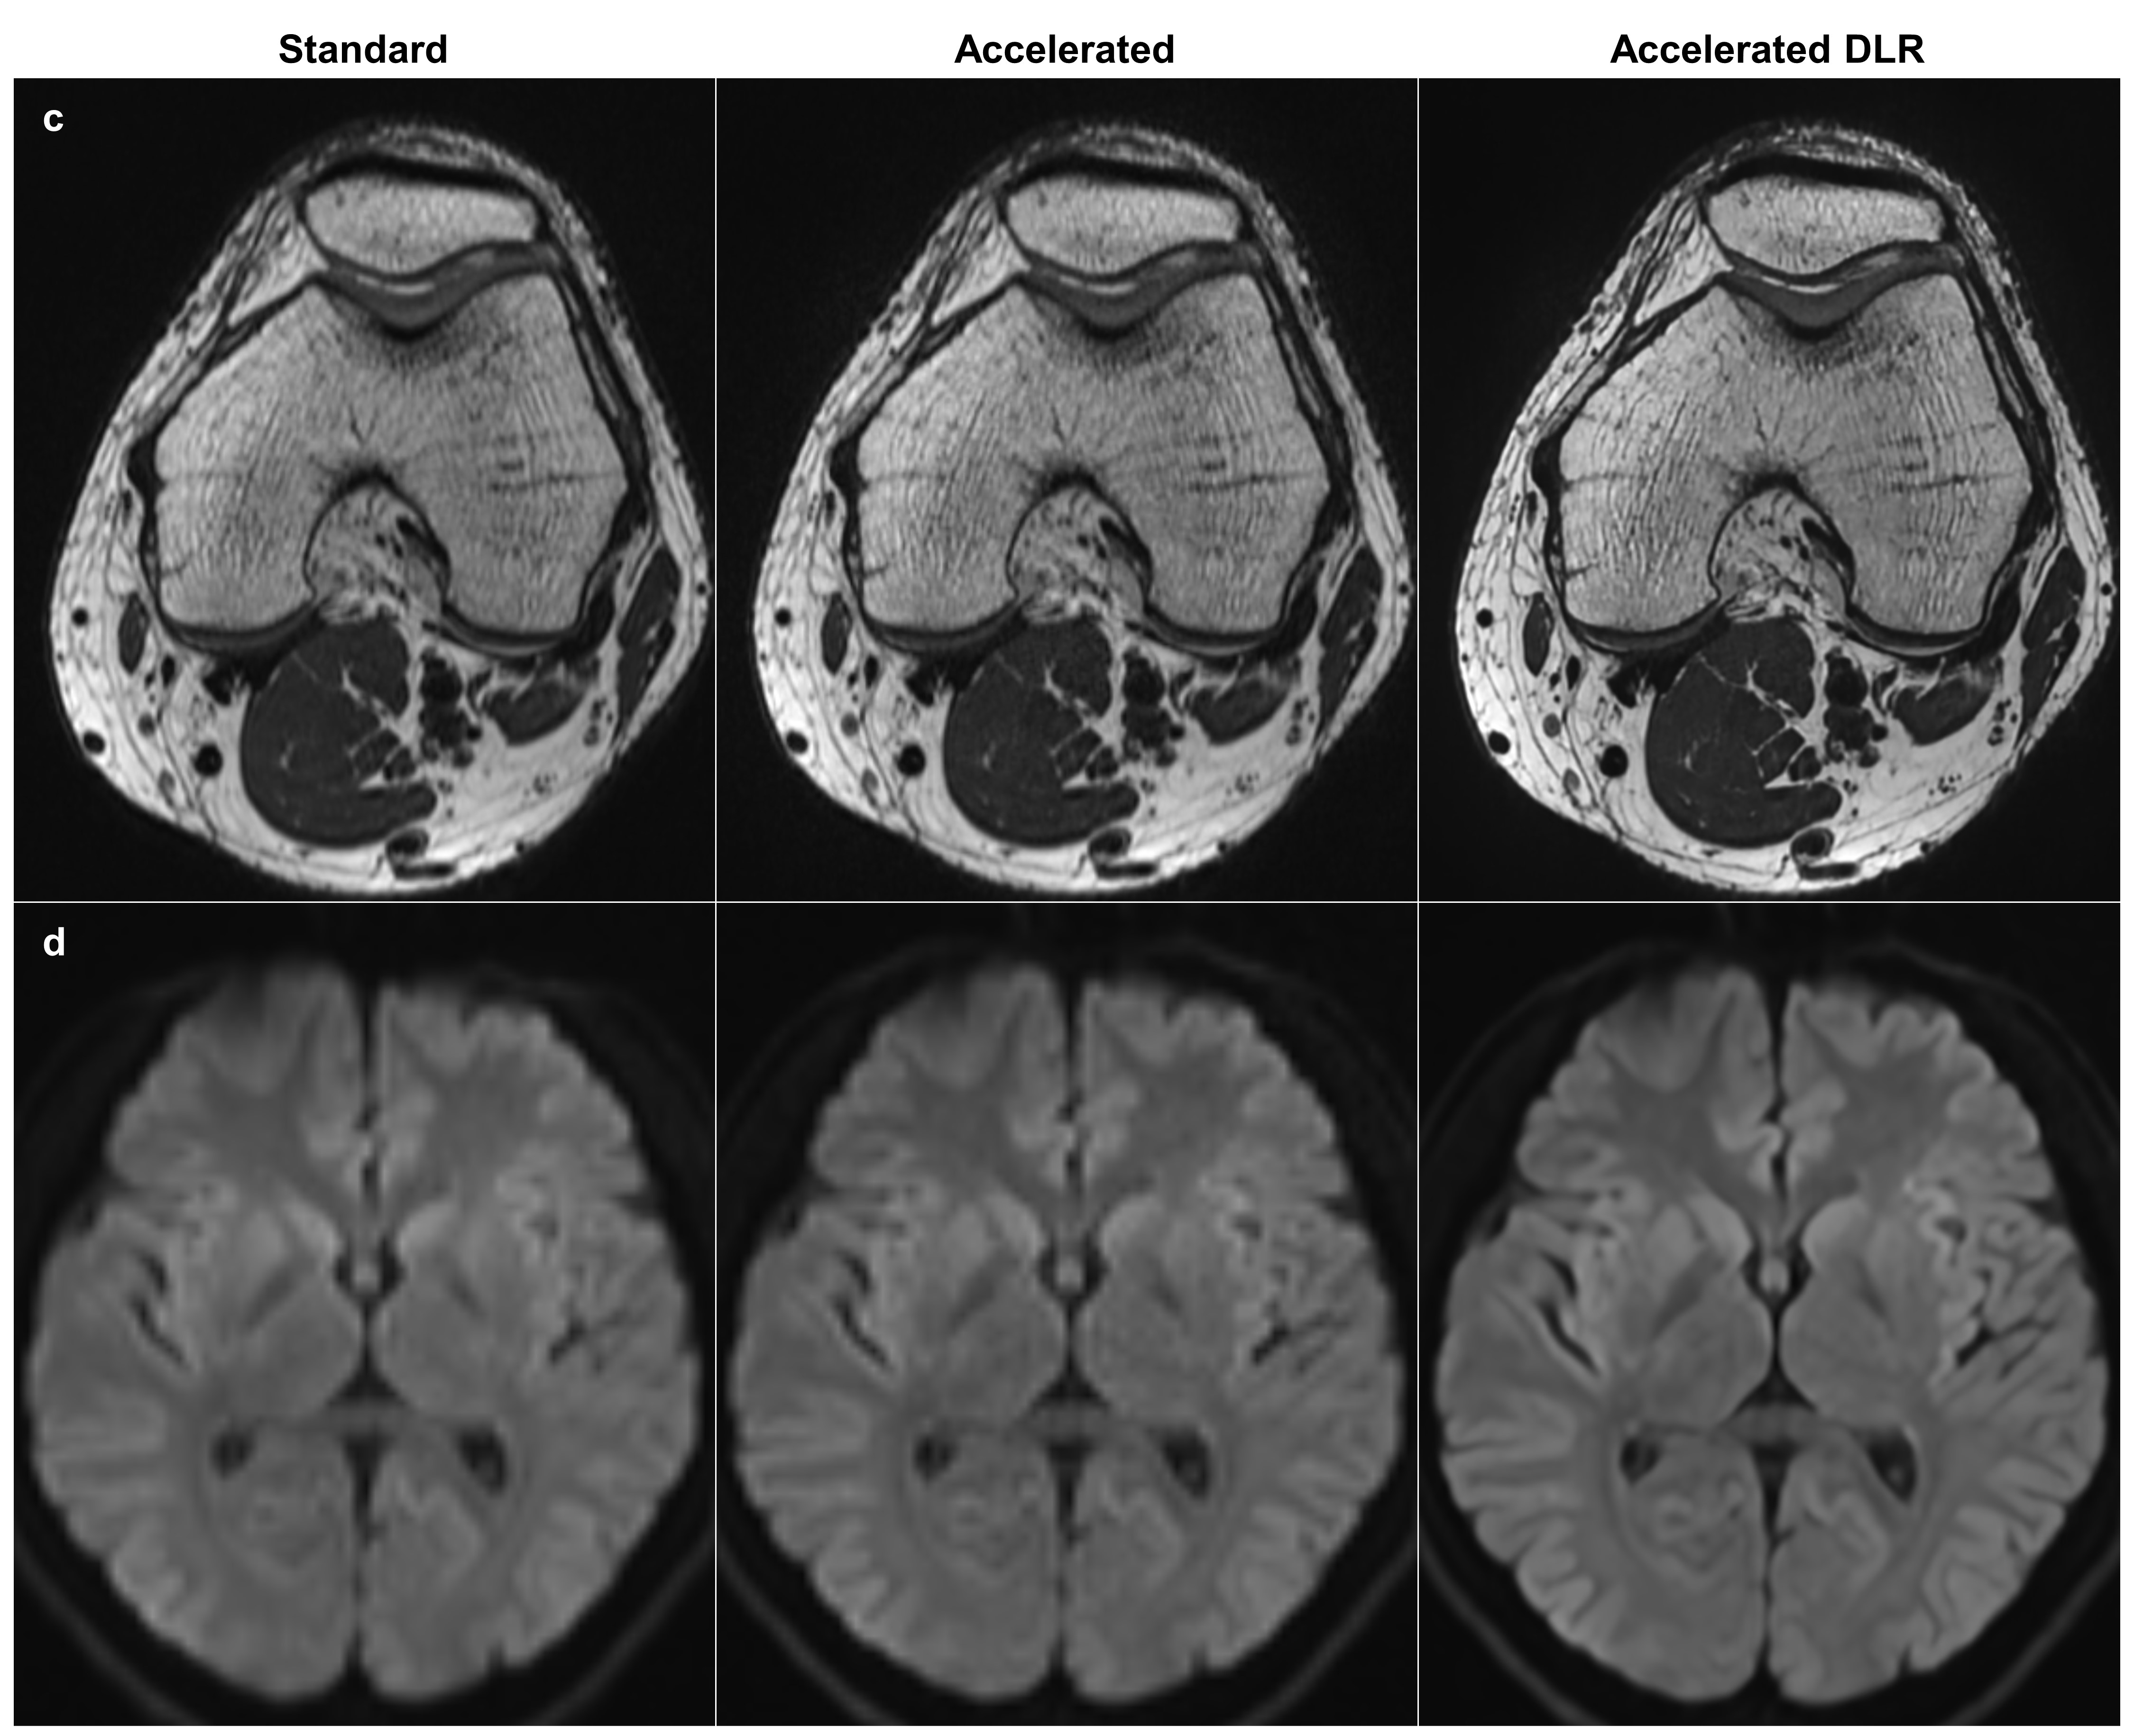

3.7 Scan time reduction across anatomical regions

To explore the model’s potential in reducing scan time, we acquired image pairs from standard and accelerated protocols across four different anatomical regions: heart, lumbosacral plexus, knee, and brain, on a 3.0T MR scanner (MAGNETOM Skyra, Siemens Healthineers) with 30-channel body coil/32-channel spine coil, a 32-channel spine coil, a 15-channel transmit/receive knee coil, and a 64-channel head/neck coil, respectively. The accelerated protocols were optimized from standard protocols to reduce scan time and increase spatial resolution, which resulted in increased noise. Table 2 summarizes the scan parameters and scan times for each protocol. After applying DLRs to the accelerated images, we visually compared them with the corresponding standard images. A noise reduction factor of 2.0 was used for the heart and knee, while a factor of 3.0 was used for the lumbosacral plexus and brain. For the knee T2WIs, a 1 mm thick multiplanar reformation (MPR) image was generated from each source image (standard, accelerated, and accelerated DLR).

Figure 9 presents standard, accelerated, and accelerated DLR images across four anatomical regions. The DLR heart cine image shows improved delineation of papillary muscles in the left ventricle. The DLR lumbosacral plexus neurography image provides clearer visualizations of nerve roots, dorsal root ganglia, and spinal nerves. The DLR knee T2WI reveals a more distinct depiction of the overall soft tissues. The DLR brain DWI exhibits superior apparent resolution, particularly in the delineation of sulci. Notably, it also demonstrates reductions in geometric distortion artifacts in the frontal lobe, attributed to the increased GRAPPA factor. In all cases, the accelerated DLR images exhibit equivalent or reduced noise levels compared to the standard images.

Refer to caption

Figure 9: Visual comparison between standard, accelerated, and accelerated DLR images across different anatomical regions. The accelerated protocols were optimized from standard protocols to reduce scan time and increase spatial resolution, which resulted in increased noise. (a) Heart cine images where each slice was acquired in a single breath-hold, with breath-hold times of 12 seconds for standard and 9 seconds for accelerated scans. (b) Lumbosacral plexus neurography images with scan times of 369 seconds for standard and 219 seconds for accelerated. (c) Reformatted knee T2-weighted images with scan times of 321 seconds for standard and 185 seconds for accelerated. (d) Brain diffusion-weighted images with scan times of 52 seconds for standard and 32 seconds for accelerated. In all cases, the accelerated DLR images exhibit boosted perceived resolution and either equivalent or reduced noise levels compared to the standard images. DLR, deep learning reconstruction.

Figure 9: Visual comparison between standard, accelerated, and accelerated DLR images across different anatomical regions (continued).